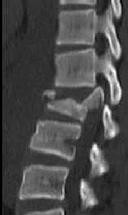

Figures 1 and 2 are CT scans obtained from a 68-year-old man who has had

progressive neck pain and stiffness, worsening gait imbalance, upper extremity weakness, early muscle fatigue, difficulty with fine motor control, and difficulty with activities of daily living over the past few years. On physical examination, he has a wide based stiff legged gait, generalized upper extremity weakness, dense sensory loss in the upper and lower extremities, and markedly brisk reflexes. What is the most appropriate treatment for this patient?

4. Posterior cervical laminoplasties from C3-6 Discussions: D

This patient has progressive myelopathy secondary to ossification of the posterior longitudinal ligament. Diagnostic imaging reveals multilevel cervical cord compression from C4-6. The patient has maintained reasonable cervical lordosis. A posterior procedure such as multilevel laminoplasty

decompresses the spine, is motion preserving, and has a low complication rate. Observation and cervical epidural injections are not viable options in patients with progressive myelopathy. Anterior cervical decompression, including corpectomy, is an option; however, anterior procedures have an increased risk of complications such as dural tear or cerebrospinal fluid leak. The axial CT image shows a "double layer" sign, which is consistent with dural ossification and increases the risk of dural injury with anterior decompression